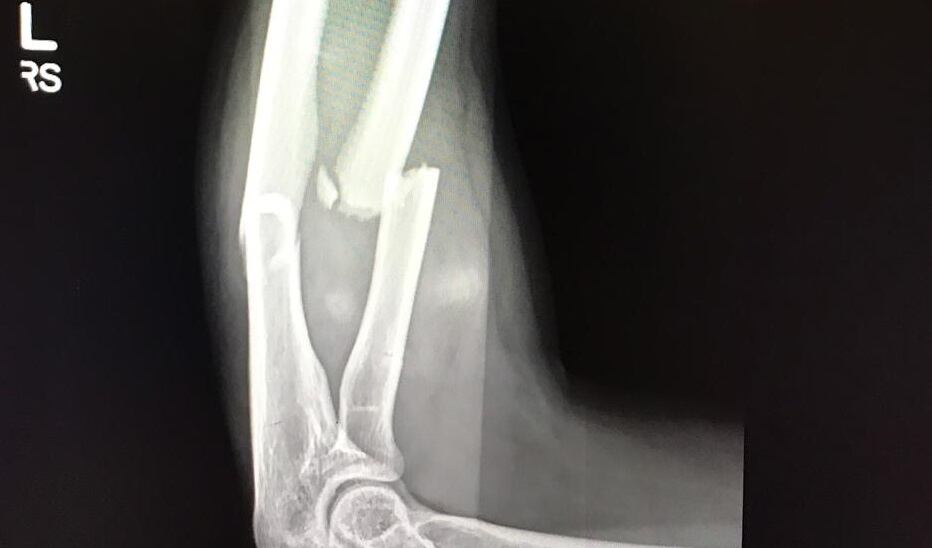

Un caso de estos es el de la portera costarricense Noelia Bermúdez, quien el 5 de octubre del 2018 sufrió una fractura en el brazo izquierdo en medio de un partido.

En una jugada de esas llamaas “sin gracia” en un juego contra la selección de Cuba, en el premundial rumbo a Francia 2019, la arquera cayó mal, con el peso del cuerpo sobre el brazo y se lo partió casi a la mitad.

Debieron llevarla de inmediato para un hospital en Texas, Estados Unidos, donde fue operada casi de inmediato.